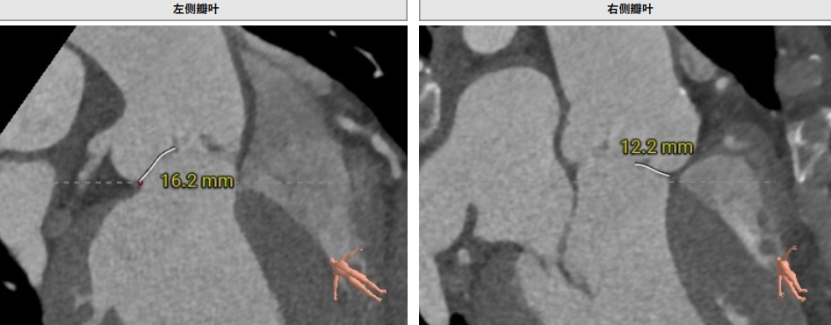

术前CT评估

Type I型三叶瓣,大瓣环,主动脉窦部扩张,近似横位心,双侧冠脉点状钙化。

双侧冠脉开口高度可,左侧瓣叶偏长,窦部空间可,无冠脉遮挡风险。

(入路概览)

输送器可调弯30°左右。